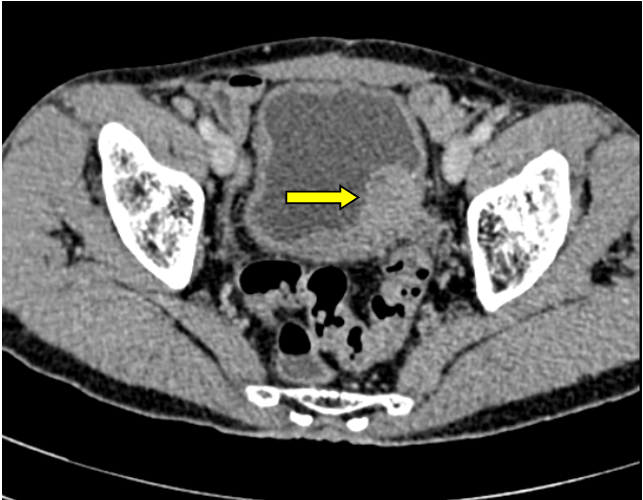

Sau gần 4 giờ phẫu thuật, khối u cùng toàn bộ bàng quang của người bệnh đã được cắt bỏ, bàng quang mới được tạo hình từ một đoạn hồi tràng. Hiện tại sau 4 ngày hậu phẫu, sức khỏe người bệnh ổn định.

Hình ảnh bàng quang tân tạo